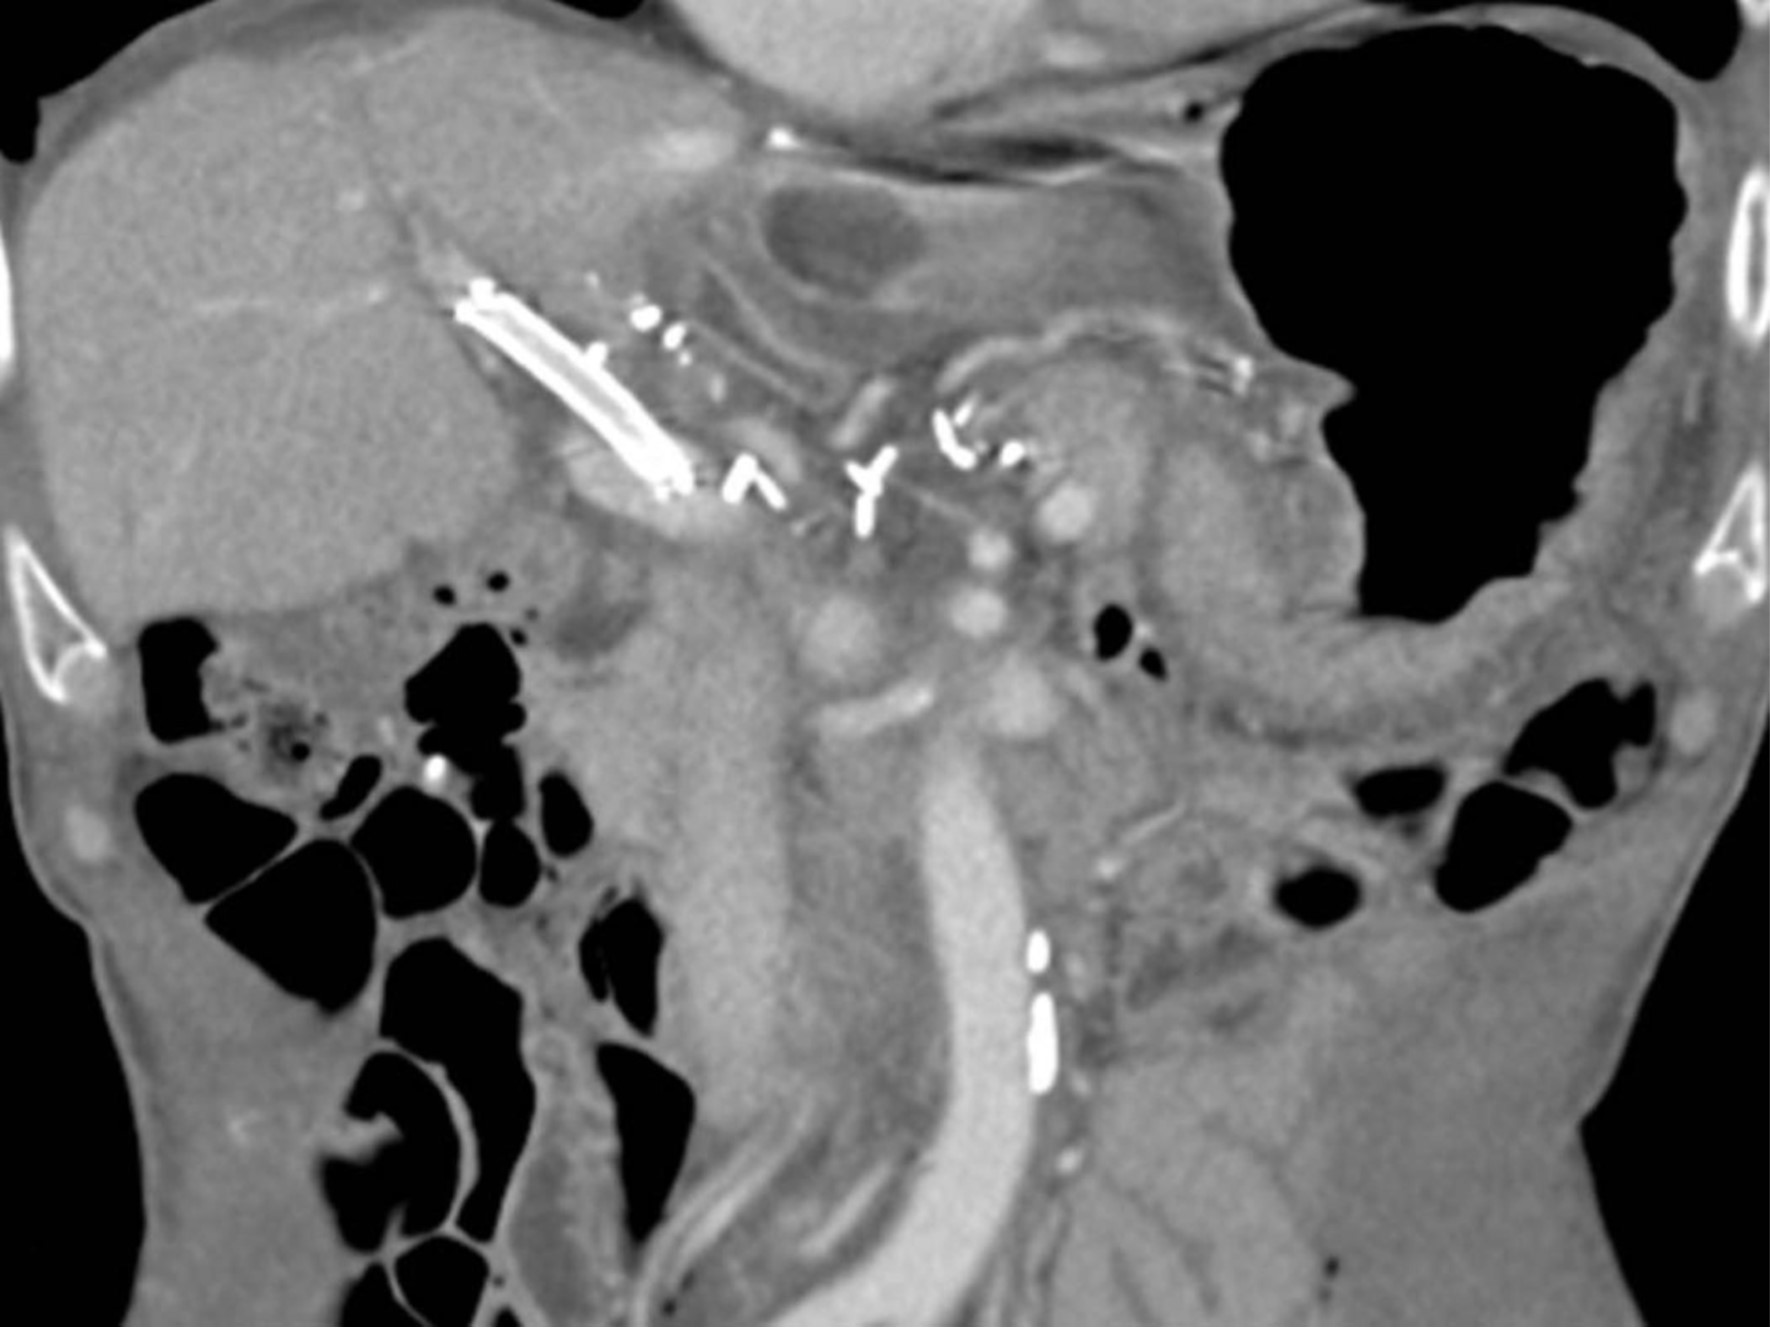

복부 CT 문맥기 영상에서 재구성한 관상면 영상에서, 우전간문맥(right anteriorportal vein)의심한 협착이 보임(Fig 1).

Fig. 1.

Fig.1 Coronal reformatted image from portal venous phase CT scan shows severe stenosis of right ant. portal vein(arrow).